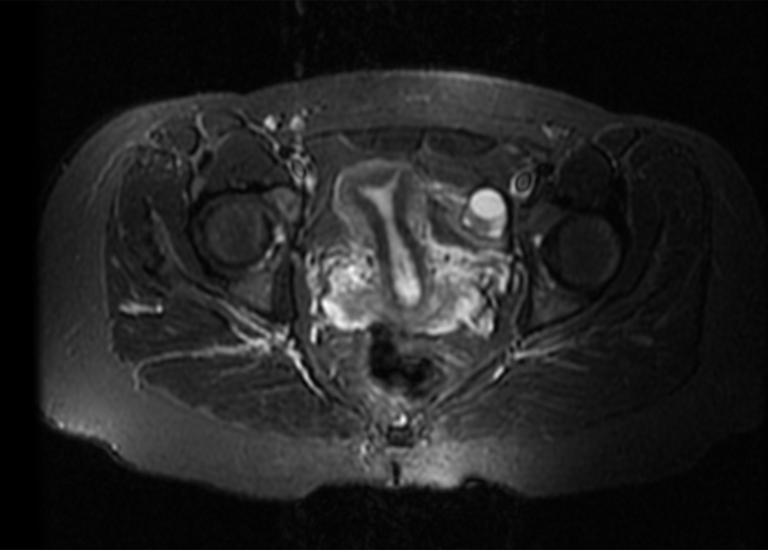

What kind of things can this incredible technology uncover? For women, a pelvic MRI is a game-changer for understanding conditions affecting the uterus, ovaries, and cervix. It's instrumental in diagnosing and staging conditions like fibroids (those common, often harmless, but sometimes problematic growths), endometriosis (where uterine tissue grows outside the uterus, causing pain), and even various forms of gynecological cancers. It can also shed light on pelvic pain causes and infertility investigations. For men, it's crucial for examining the prostate gland, seminal vesicles, and bladder, helping to detect conditions such as prostate cancer, inflammation, or other structural abnormalities. It's also valuable in cases of pelvic trauma or unexplained pelvic pain for both genders.